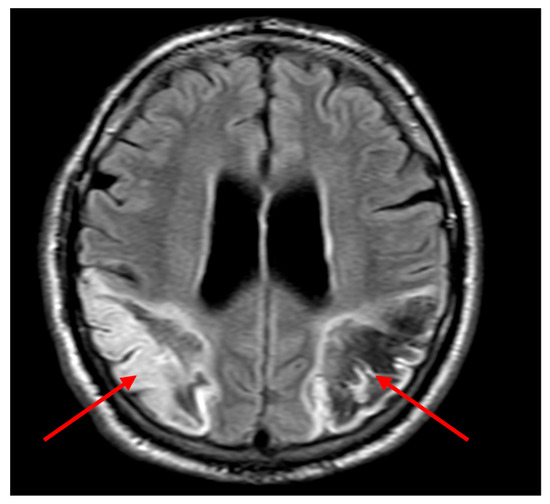

Follow-up contrast-enhanced MRI confirmed stable bilateral parietal infarcts with no evidence of new lesions (Figure 3).

Figure 3. Fluid-attenuated inversion recovery (FLAIR) MRI images showing extensive bilateral parietal ischaemic infarcts, with haemorrhagic transformation (red arrows), confirming the chronicity and bilateral nature of the lesions.